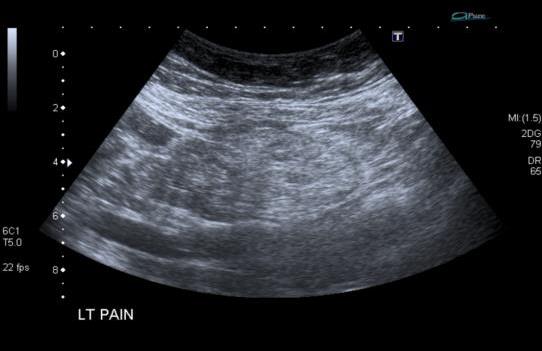

Representative sonographic images of the abdominal scan are shown below:

![]() |

Figure 3. Transverse image through the left upper quadrant |